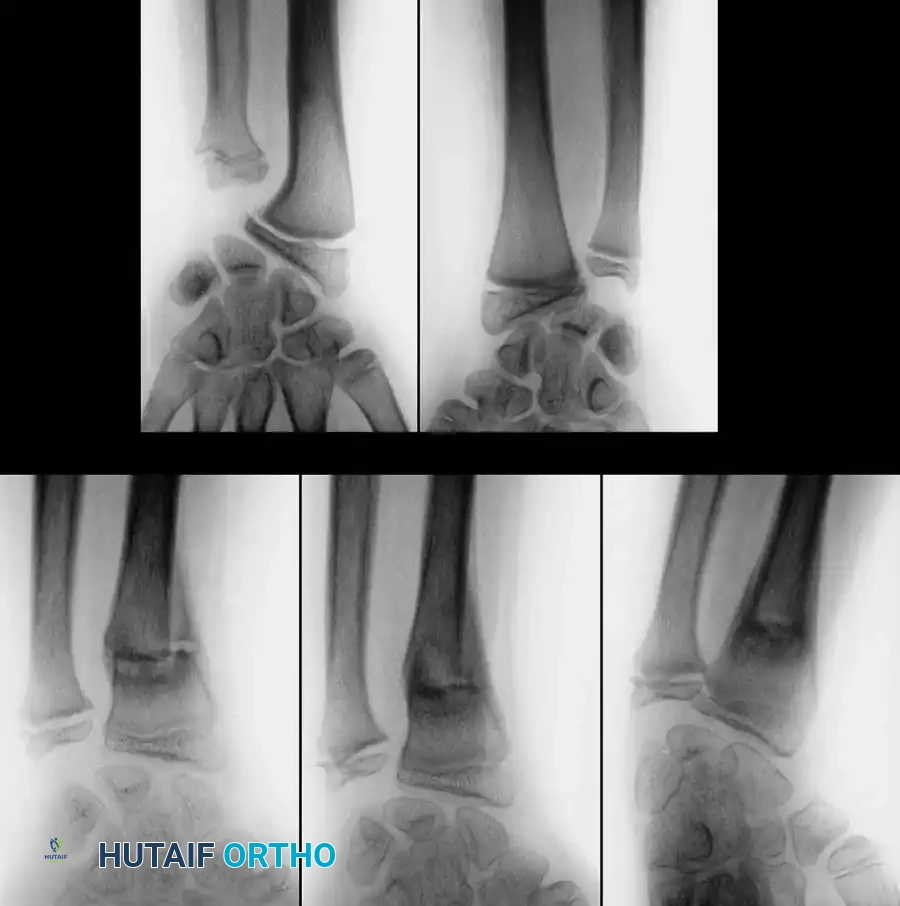

FRACTURES OF THE DISTAL THIRD OF THE FOREARM

Epidemiology and Pathoanatomy

Fractures of the distal third of the forearm are exceptionally common. Blount noted that approximately 75% of all pediatric forearm fractures occur in this region. The vast majority are dorsally displaced (Colles-type equivalents) and occur in the plane of motion of the radiocarpal joint. Because they are in the plane of joint motion and close to the highly active distal radial physis, they remodel remarkably well, provided the child has sufficient growth remaining.

Physeal Injuries and Growth Arrest

In addition to metaphyseal both-bone fractures, physeal fractures of the distal radius and ulna are frequently encountered. Salter-Harris type I and II fractures are the most common; types III and IV are exceedingly rare.

While these physeal injuries typically respond well to closed reduction and casting, complications can arise. Lee et al. reported cases of premature closure of the distal radial physis following either severe physeal compression injuries (Salter-Harris type V) or repeated, forceful attempts at closed reduction.

Surgical Warning: Repeated manipulation of a pediatric distal radius fracture significantly increases the risk of iatrogenic physeal damage. If the initial reduction achieves greater than 50% apposition with acceptable alignment, further forceful attempts at perfect anatomical reduction should be strictly avoided.

Zehntner et al. described growth disturbances caused by partial closure of the distal radial physis, leading to a pseudo-Madelung deformity. This tethering effect results in ulnar deviation of the radius and relative ulnar overgrowth.